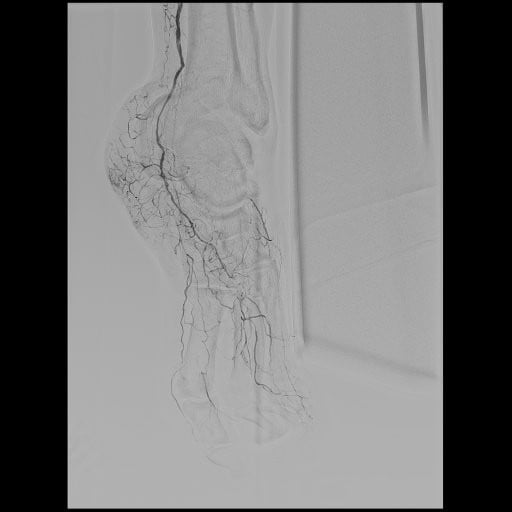

血管造影検査

当院では、血管の状態を詳しく調べたり、カテーテルを使って治療を行う「血管造影検査・治療(IVR)」を実施しています。専用の血管造影装置は2台あり、1台は心臓や足の血管など循環器専用、もう1台は脳や腹部などの頭腹部用です。令和7年4月からは、頭腹部用の装置を最新機種に更新し、より高精度で安全な検査・治療が可能となりました。主な対象疾患は、心筋梗塞、下肢動脈閉塞、脳梗塞、脳動脈瘤、頸動脈狭窄などで、これらに加え、肝臓や子宮の腫瘍、外傷などに対する止血術(TAE)など全身の病気に対応しています。経験豊富なスタッフが担当し、患者さんの負担を軽減しながら、安全で質の高い医療を提供しています。